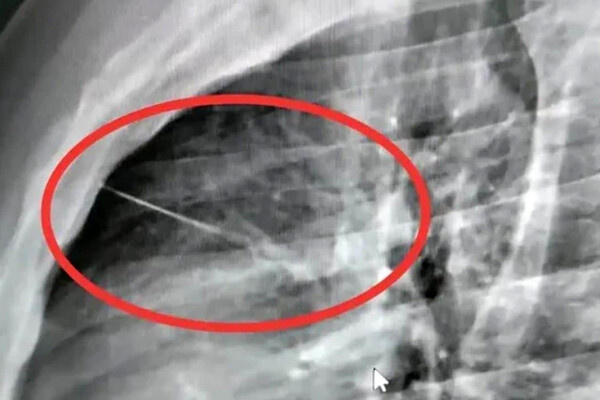

Рентген в местной больнице, куда сначала доставили тайца, показал острый посторонний предмет рядом с сердцем, позже медики установили, что это игла длиной около семи сантиметров. Пациента срочно перевели в крупную больницу Бурирама, чтобы провести высокорисковую операцию по удалению инородного тела.